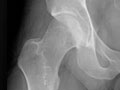

- X-rays. Pictures of the bones in a joint, such as the

hip

or knee, are taken to look for cartilage

damage.